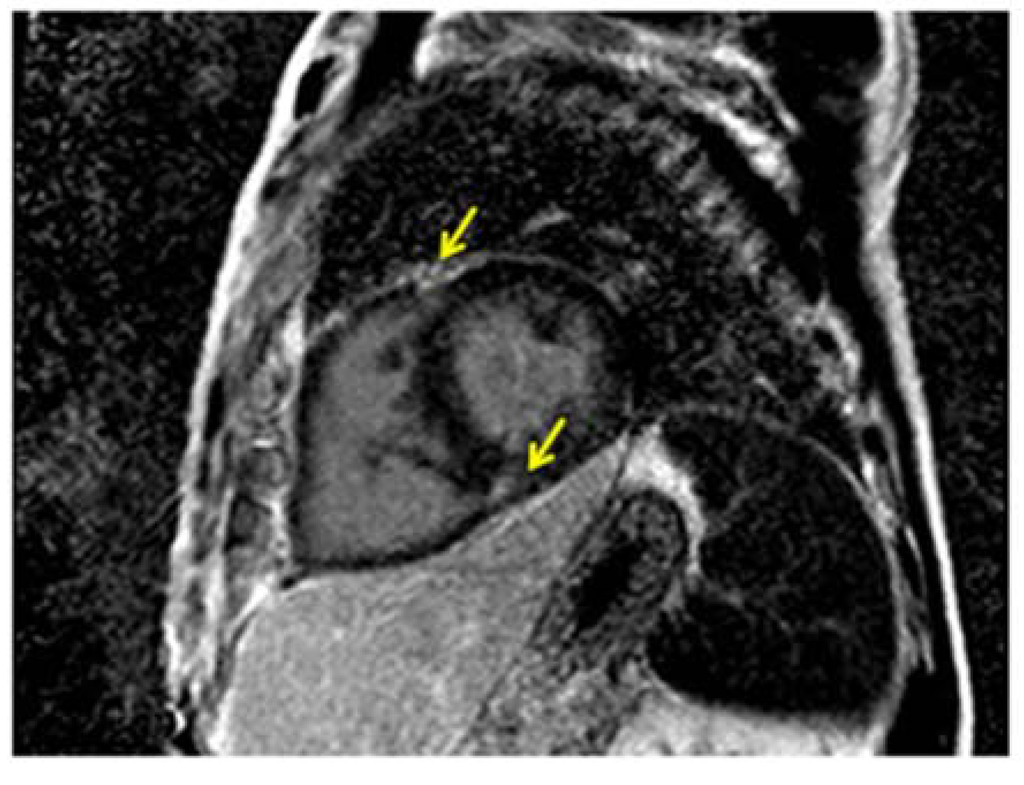

The presence of late gadoliniun enhancement (LGE) pattern in the RV myocardium of patients with PH has been first described by McCann and colleagues in 2005 []. LGE imaging shows a characteristic retention of gadolinium at the septal insertion (junctional pattern) [,,], without any retention in the free wall [] (Figure 7). Looking for LGE deposition in RV free wall of normal subjects or in pathologies like arrhytmogenic RV cardiomyopathy is difficult, because of partial volume effects due to the fact that the RV wall is particularly thin. Conversely, PH patients show thick RV walls, which does not pose any difficulty in nulling the RV myocardium. Further, LGE junctional pattern is not specific for PH, but it has been found in other pathologies like hypertrophic cardiomyopathy [,]. The etiology of this gadolinium retention remains to be clarified. The first hypothesis was the presence of fibrosis. Bradlow et al. [] examined the heart of a patient with idiopathic PH and LGE junctional pattern at autopsy. They found increased collagen and fat between fiber bundles (plexiform fibrosis) consistent with myocardial disarray, but no pathological fibrosis. Myocardial disarray is common in healthy people at the interventricular junction site, but it appears particularly exaggerated in PH patients. A recent prospective observational study [] demonstrated a moderate correlation among the presence of LGE junctional pattern and paradoxical septal motion, assessed by echocardiography, associated to a weaker correlation with RV function parameters. This data suggest that the abnormal interventricular septal motion, rather than the elevated RV pressure and the consequent remodeling may be the mechanism underlying the appearance of LGE junctional pattern. The reported occurrence of LGE junctional pattern in PH is not univocal, it ranges from 69% [] to 100% []. The amount of the LGE junctional pattern has been demonstrated to be moderately related to the amount of RV dysfunction measured as ejection fraction, stroke volume and end-systolic volume [] and it appears to predict RV remodeling in response to increased afterload []. Moreover, patients with the junctional pattern of the LGE are significantly more likely to experience a worse clinical outcome than those without this marker. LGE junctional pattern has been reported to be related to worse outcome in term of death, need of lung transplantation, initiation of prostacyclin therapy, and decompensated RV heart failure, stratifying prognosis [].

Figure 7.

CMR imaging of a PH patient showing the typical septal junctional pattern of late gadolinium enhancement (yellow arrows).